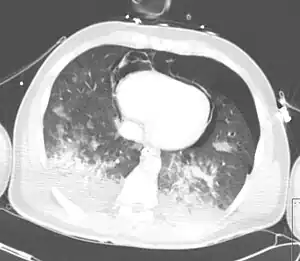

| CT scan showing pneumopericardium with pneumomediastinum, pneumothorax, hemothorax, and pulmonary contusion after severe chest trauma[1] | |